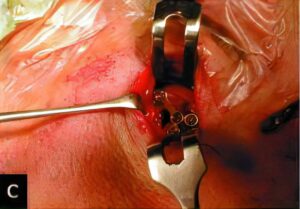

顎関節内の洗浄療法や手術療法が必要と判断した場合には、当院の関連機関である新潟大学医歯学総合病院顎顔面外科口腔外科診療室にご紹介しています。

外傷

連携病院である沼田脳神経外科循環器科病院は、救急指定病院ということもあり、当院でも顎口腔領域の骨折や裂傷、歯牙破折や脱臼などの患者さんの治療も行っております。